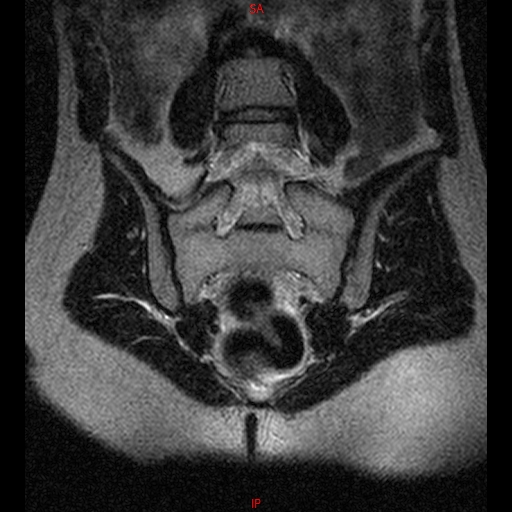

• RESONANCIA NORMAL SACROILIACAS COR T2